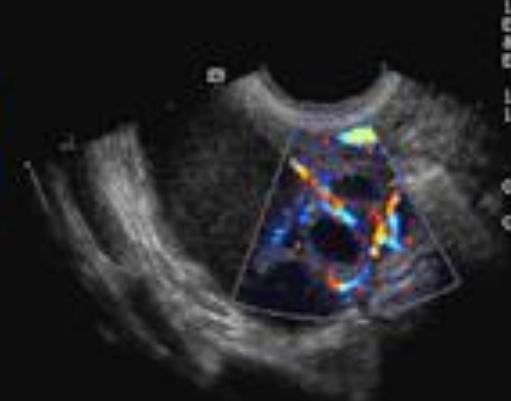

Cuando sonográficamente observamos una estructura tubular en la pelvis,

la técnica Doppler es útil para diferenciar las trompas de falopio de unas venas dilatadas.

un engrosamiento nodular e irregularidad en el trompa y color Doppler muestra hiperemia en las paredes engrosadas de la trompa.